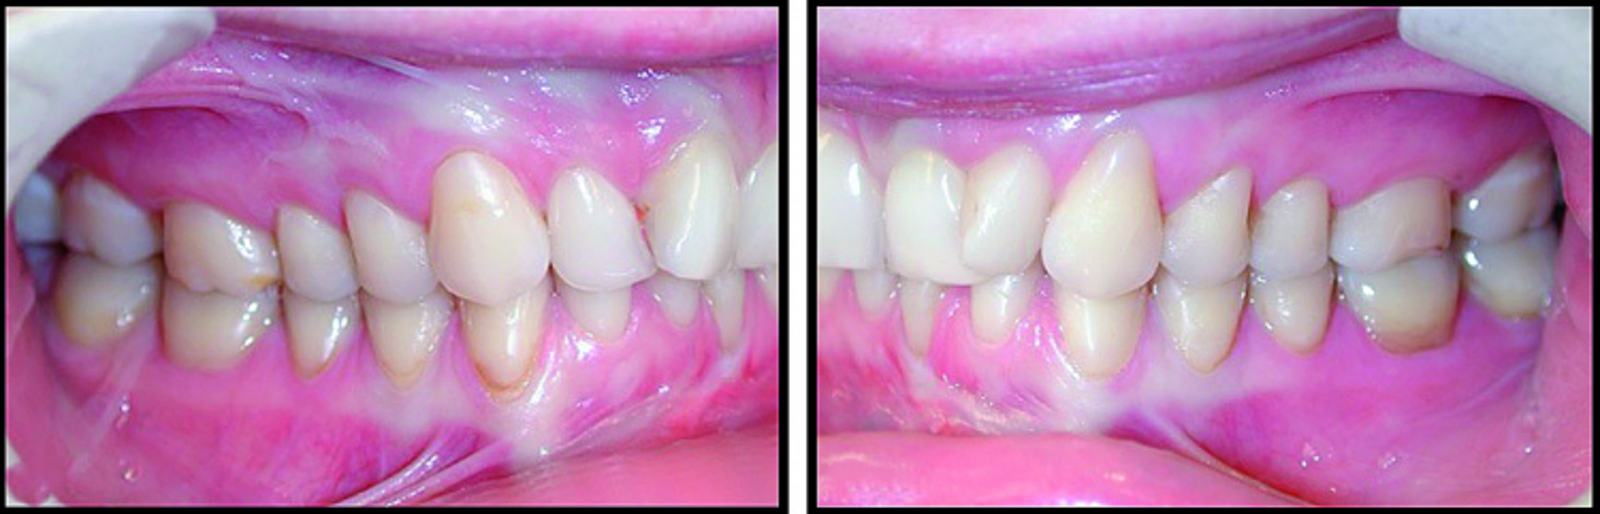

BiTurbo2 system for rapid deep overbite correction